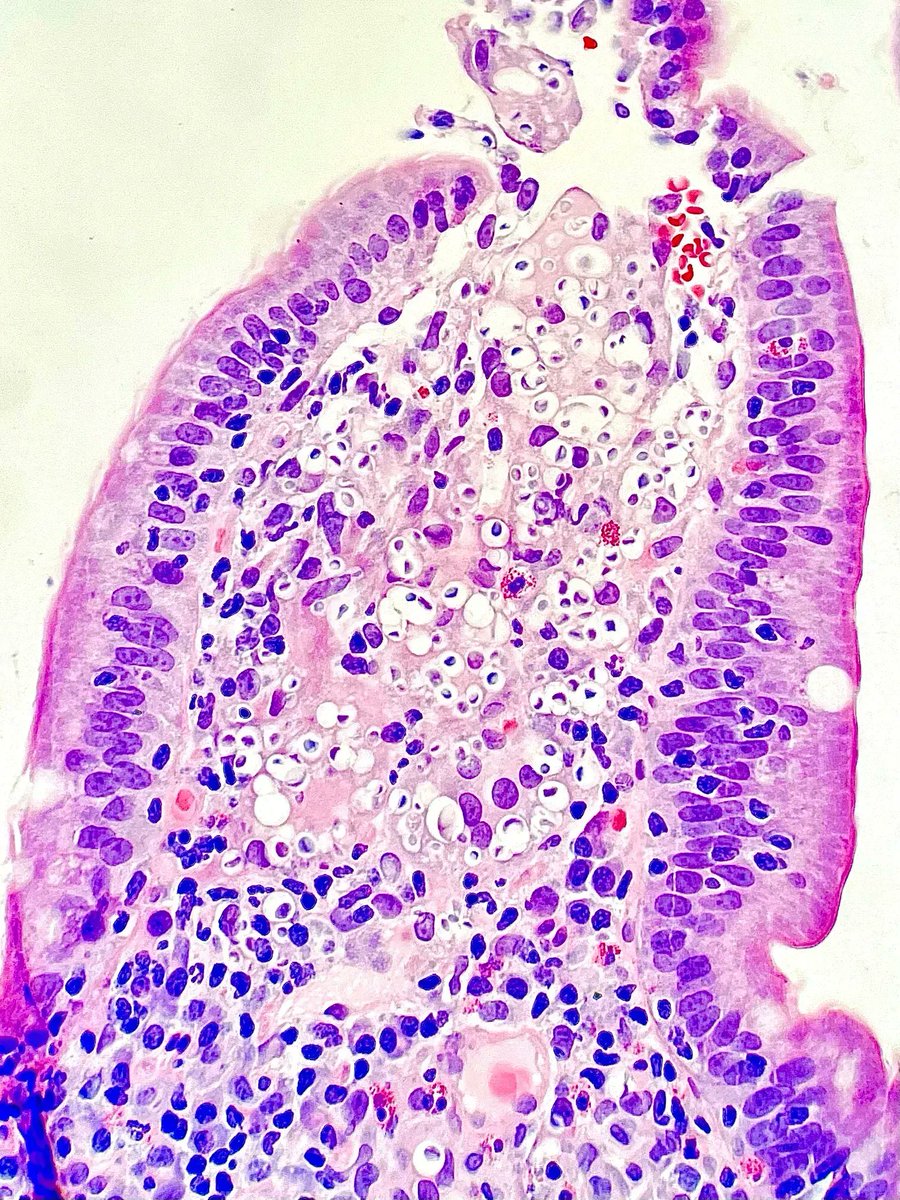

Gross Spotter craze- Adrenal myelolipoma, admixture of adipose tissue and haemorrhagic areas. #APCON2022 #APCON2022PathTweet Adriana Ancer Padma Priya J Aditya Agnihotri 🇮🇳 Archana bhat Annie A. Wu, MD, PhD Frank Ingram, MD Daisy Maharjan Sandeep Mathur Department of Pathology, AIIMS, New Delhi Dr Anila Sharma Arunima Deb, MD